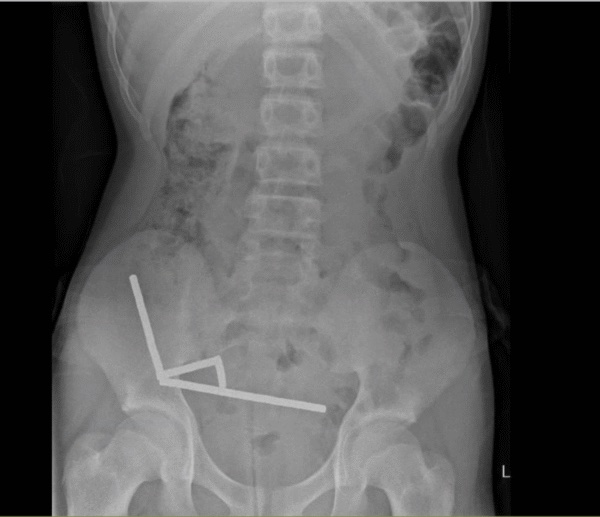

Ακτινογραφία έδειξε τέσσερις γραμμικές αλυσίδες μαγνητών σε διαφορετικά σημεία του εντέρου. Μέσα στην κοιλιά του, οι μικροί μεταλλικοί μαγνήτες ενώθηκαν με καταστροφικό τρόπο.

Κατά τη διάρκεια του χειρουργείου, οι αλυσίδες εντοπίστηκαν σε διάφορα τμήματα του λεπτού εντέρου και του τυφλού, του τμήματος του παχέος εντέρου που βρίσκεται στην αρχή του και συνδέεται με το λεπτό έντερο.